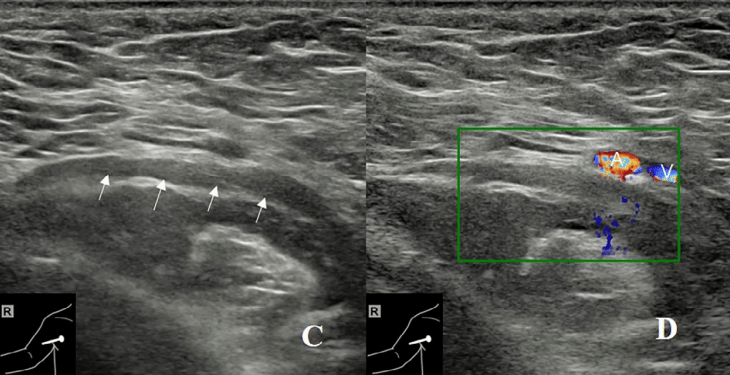

2)肩胛下肌的前方:患者平躺,肩部完全外展以暴露整个腋窝。探头水平放置在肱骨头上。观察到肩胛下肌位于肱骨头的上方,腋神经(AN)的短轴位于肩胛下肌和背阔肌之间,呈点状低回声(图3A)。旋转探头,显示腋神经在肩胛下肌表面的长轴切面,呈带样低回声(图3B)。

图3A:探头水平放置在肱骨头(HH)上。可见肩胛下肌(SubS)位于肱骨头上方。腋神经(AN)的短轴(箭头)在肩胛下肌(SubS)和背阔肌(LD)之间呈点状低回声。

图3B:旋转探头显示腋神经(AN)的长轴(白色箭),在肩胛下肌(SubS)表面呈低回声带。A,腋动脉;V,腋静脉

3) 腋动脉后方:探头沿腋神经向内侧移动至腋血管后方,有时可见腋神经由臂丛后束发出(图3C)。将探头与腋神经平行并轻调探头位置,可见旋肱后动脉位于腋神经旁,并可追溯至其起源于腋动脉(图3D)。

图3C:沿腋神经(AN)(白色向上箭)向内侧移动探头至腋动脉(A)和静脉(V)的后方。

图3D:轻调探头位置,可见后旋肱后动脉(PCA)位于腋神经(AN)(箭头)旁,可追溯至其起源于腋动脉。